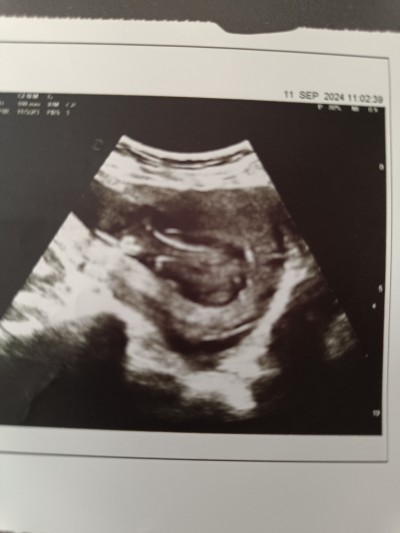

12 haftalık 3 günlükdu doktor bu haftalarda beli olmaz bir ay sonra gel beli olur dedi bu kağıtlardan bebeğin nerde olgunu bile anlamıyorum ben siz nasıl görüyorsunuz birde cinsiyete bakıyorsunuz çok merak ediyorum :)

Ultrasonu çok kötü çekmiş. Benimde bebeğime ait hiç güzel ultrason görüntüsü yok.